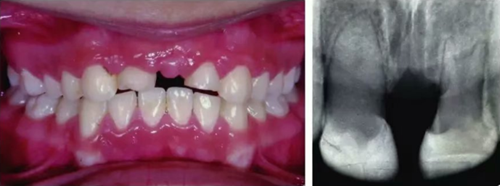

初步正畸牽引嵌入的上頜側(cè)切牙并重新獲得切牙空間。上頜側(cè)切牙的預后顯示有嚴重的牙根吸收。因此需要拔除上頜側(cè)切牙(圖3)。

圖3. 影像學顯示上頜側(cè)切牙牙根吸收

6個月后,移植牙的根尖片顯示治療期間沒有出現(xiàn)牙根吸收的影像?;颊邲]有出現(xiàn)不適,沒有發(fā)生牙齦炎。在23個月期間沒有進行任何修復完成治療,達到I類關(guān)系(圖5和圖6)。

圖5. 正畸后影像學檢查

圖6. 正畸后口內(nèi)照